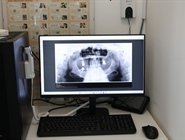

Sve se radi uz pomoć najsuvremenije tehnologije, uključujući digitalni 2D ortopan, 3D skenere i precizno računalno glodanje, što znači – nema više neugodnih otisaka ni višestrukih dolazaka.